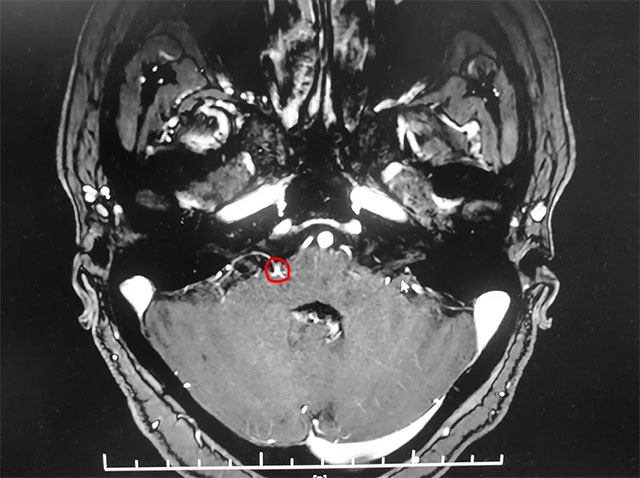

▲ 患者右侧面神经与周围小血管关系密切

入院后,经面神经MRTA平扫+增强检查显示,患者右侧面神经与周围小血管关系密切。在对患者病情及影像学资料进行评估,并告知患者及家属手术风险后,上海蓝十字脑科医院神经外科主任沈建康教授团队为患者实施了面神经微血管减压手术。